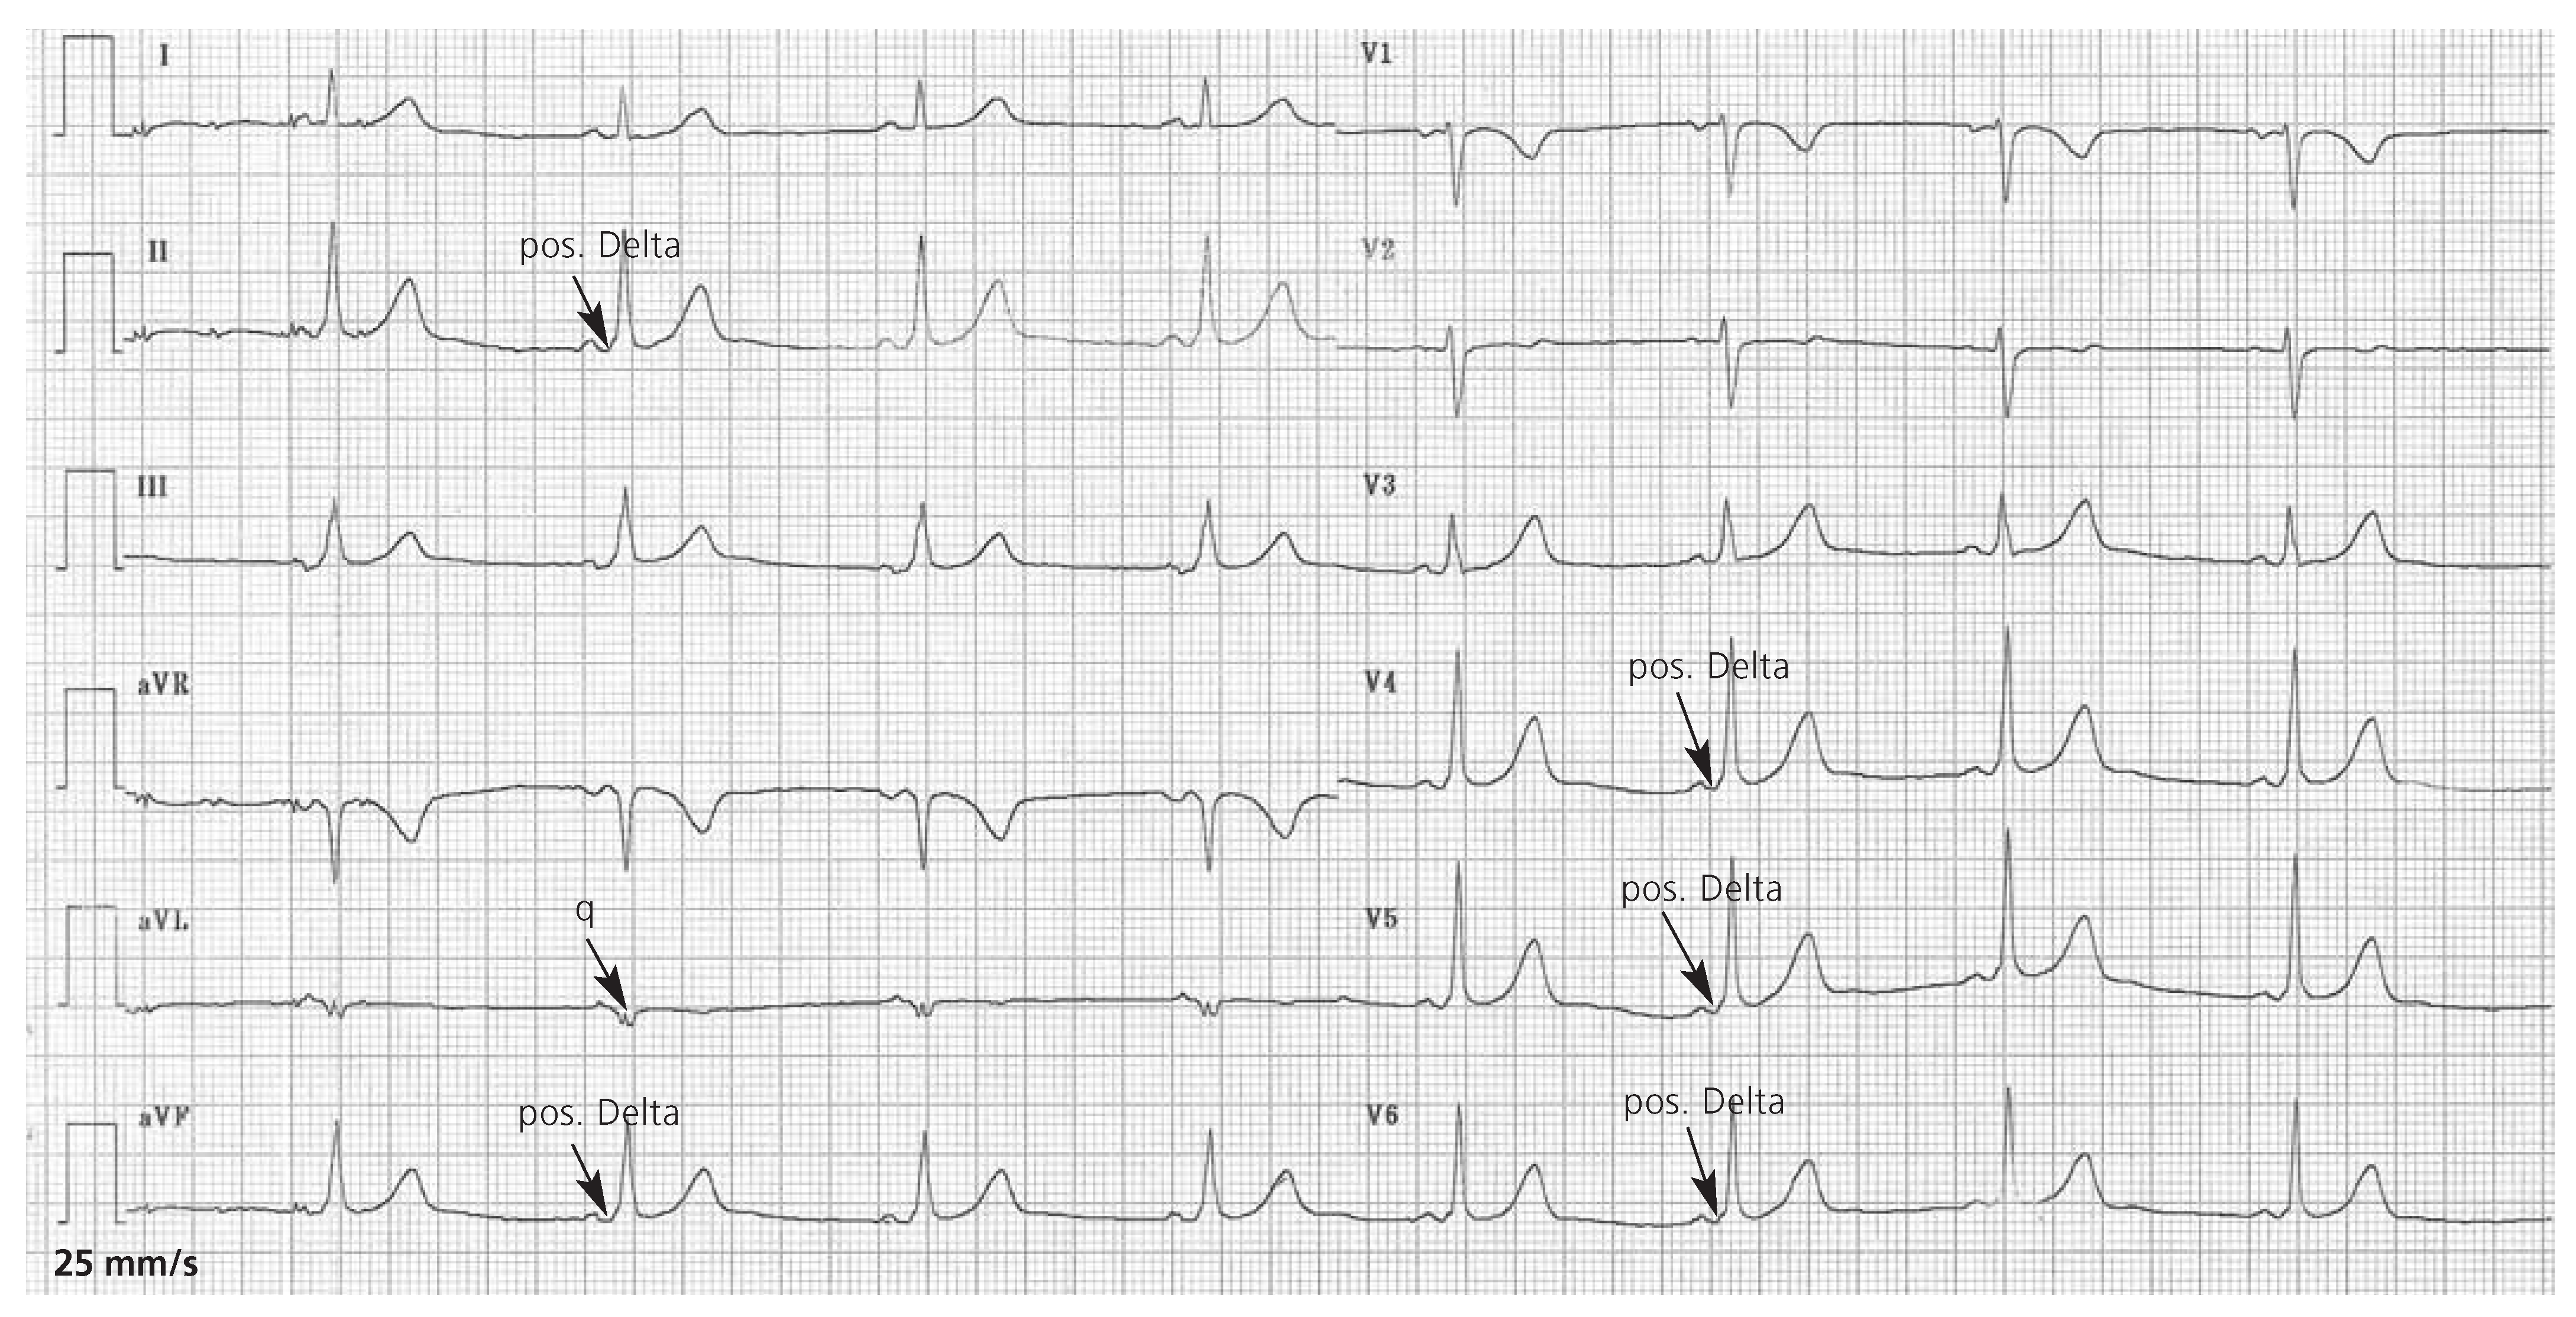

Im EKG (Figure 1) sehen wir eine Tachykardie um 170/min mit schmalen und breiten Komplexen, welche eine inferiore Hauptachse und Rechtsschenkelblockmorphologie aufweisen. Während der Schmalkomplextachykardie ist eine Mittellage vorhanden. Die Brustwandableitungen zeigen eine regelrechte R-Progression ohne Erregungsrückbildungsstörungen. Die eingestreuten Breitkomplextachykardien weisen teilweise einen gleichen RRAbstand auf. Sie lassen an eine ventrikuläre Tachykardie aus dem linksventrikulären Ausflusstrakt denken.

Figure 1.

Das 12-Kanal-EKG bei Eintritt zeigt eine Tachykardie bis 214/min mit schmalen und breiten Komplexen. Es handelt sich um ein Vorhofflimmern mit schneller Überleitung und intermittierender Breitkomplextachykardie.

Entsprechend dem Algorithmus zur Differenzialdiagnose einer Breitkomplextachykardie nach Brugada [1] ist eine Kammertachykardie aber unwahrscheinlich. Da eher eine absolute Arrhythmie bei vermutlichem Vorhofflimmern vorliegt, könnten die verbreiterten QRS-Komplexe durch eine Aberration bedingt sein. Allerdings entspricht die QRSAchse nicht der Insertionsstelle eines rechten oder linken Schenkels. Für eine Torsade de pointes wäre eine oszillierende QRS-Achse pathognomonisch. Die fehlende Ansprache auf Karotismassage spricht gegen eine supraventrikuläre Tachykardie. Am wahrscheinlichsten ist ein anterograd übergeleitetes Vorhofflimmern bei Wolff-Parkinson-White-Syndrom (WPW).